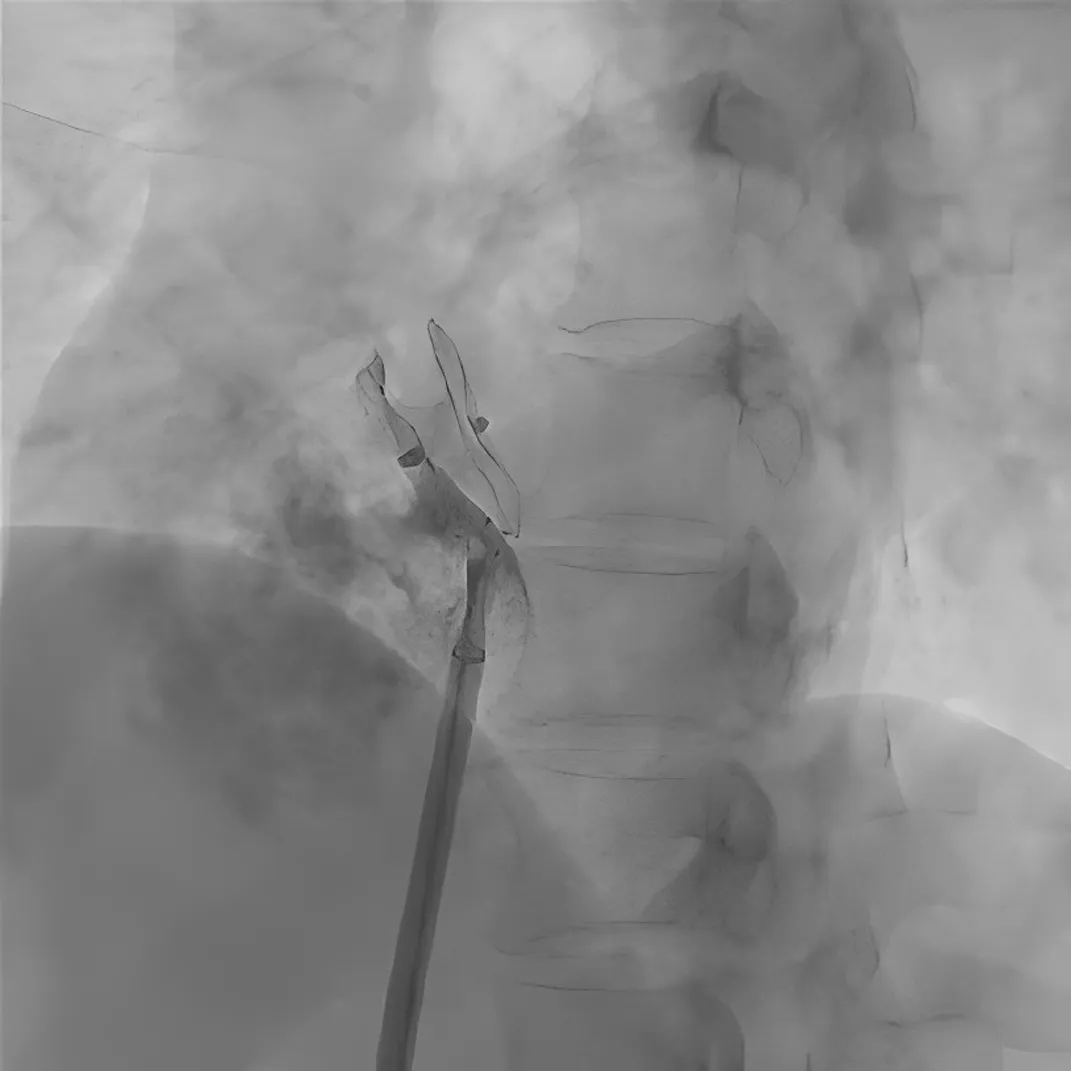

图4 使用可降解封堵器成功封堵残余分流

四个Mark显示了可降解卵圆孔未闭封堵器的位置

患者随后接受了针对卵圆孔未闭残余分流的二次封堵手术。右心导管检查测得肺动脉压力为27/10mmHg(平均压20mmHg),肺动脉造影排除了肺动静脉瘘。使用6F MPA2导管(Cordis)进行选择性房间隔造影,显示原植入的封堵器下缘存在显著右向左分流(图2)。导丝及导管成功通过残余分流处进入左心房(图3),随后将6F MPA2导管送至左上肺静脉。交换260cm加硬导丝至肺静脉,随后将12F输送鞘管沿导丝输送至左心房。成功释放一枚18/18mm对称型Memosorb可降解卵圆孔未闭封堵器(乐普医疗),有效封闭了残余分流(图4)。封堵器释放成功后立即进行选择性房间隔造影,未见明显残余分流。经胸超声心动图及透视检查均确认封堵器位置良好、形态完整(图5)。术后即刻行经胸超声心动图联合右心声学造影复查,亦未见明显残余分流(图6)。